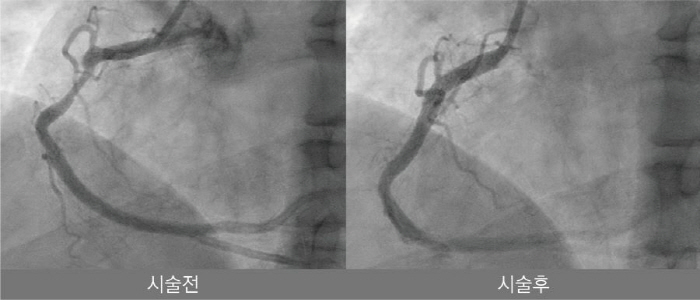

해당 시술은 심장내과 안태훈 원장과 한동훈 과장이 주도했으며 48세 남성 환자를 대상으로 시행됐다. 환자는 약 5개월 전부터 운동 시 흉통 증상이 반복적으로 나타나 나은병원을 찾았으며 관상동맥 조영술과 혈관내 초음파 검사 결과 우관상동맥 기시부에 심한 석회화를 동반한 병변이 확인됐다. 의료진은 기존 치료만으로는 충분한 확장이 어렵다고 판단해 혈관 내 쇄석술을 적용하기로 결정했다.

혈관 내 쇄석술은 특수 풍선 카테터를 혈관 내부에 삽입한 뒤 저강도 충격파를 전달해 혈관 벽에 단단히 굳은 석회 성분을 미세하게 균열시키는 최신 중재 시술이다. 이를 통해 병변의 탄력성을 개선하고 스텐트를 보다 균일하고 안정적으로 확장할 수 있어, 기존 치료법인 고압 풍선 확장이나 회전 죽종절제술에서 우려됐던 혈관 손상 위험을 줄일 수 있는 것이 특징이다.